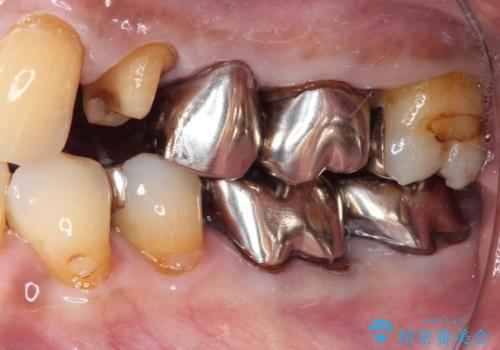

虫歯の範囲が大きく、部分的な詰め物では対応が難しいため、オールセラミッククラウンにて補綴することとしました。

外見からはあまり大きな虫歯があるようには見えなくても、X線検査をすることで、詰め物の下に虫歯が広がっていることは多々あります。

定期的に歯科医院を受診し、早期発見・早期治療をすることで、歯の神経を残す治療が可能になります。